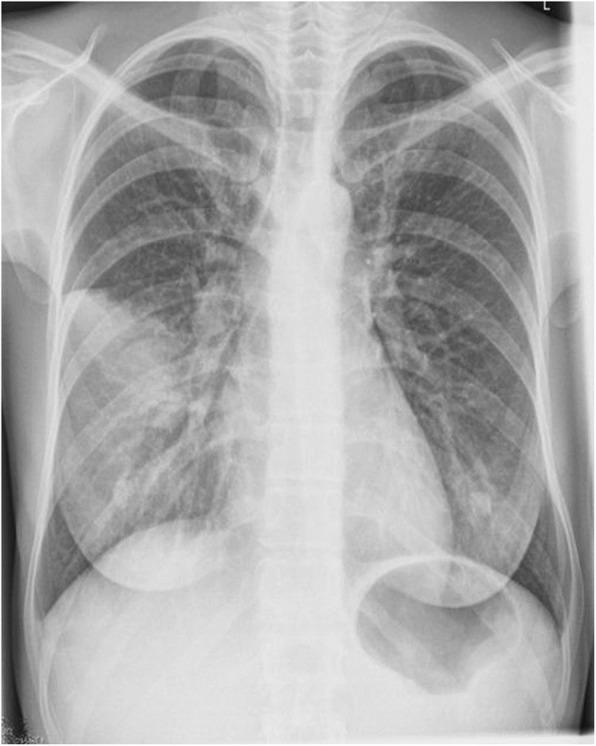

Herein, we describe a rare clinical presentation of disseminated Leptospira infection in an immunosuppressed 65-year-old woman. She was admitted to the emergency room with fever, bacteraemia, bilateral uveitis and pulmonary involvement. The patient denied outdoor activities; she only had wide exposure to faeces and urine from cats living in her home. Her medical history included idiopathic thrombocytopenic purpura (ITP) diagnosed at the age of 18. She did not respond to medical treatment, and a splenectomy was performed. At age 60, she was diagnosed with Chronic Myeloid Leukemia (CML), and was treated with a tyrosine kinase inhibitor (TKI) -Imatinib. The patient voluntarily discontinued the treatment for the last 6 months. After extensive workup, no microorganisms were identified by the commonly used stains in microbiology. The diagnosis was performed through dark-field microscopy, microagglutination test (MAT), Leptospira genus-specific PCR, the IS1500 PCR for identification of pathogenic species, and 16S based sequencing for the genus identification.

在此,我们描述了一例免疫抑制的 65 岁女性弥漫性钩端螺旋体感染的罕见临床表现。她因发热、菌血症、双眼葡萄膜炎和肺部受累而入住急诊室。患者否认户外活动;她只广泛接触家中的猫的粪便和尿液。她的病史包括 18 岁时诊断出的特发性血小板减少性紫癜(ITP)。她对药物治疗没有反应,并进行了脾切除术。60 岁时,她被诊断为慢性髓性白血病(CML),并接受酪氨酸激酶抑制剂(TKI)伊马替尼治疗。患者自愿停止治疗已有 6 个月。经过广泛的检查,微生物学中常用的染色剂未识别出任何微生物。通过暗场显微镜、微量凝集试验(MAT)、钩端螺旋体属特异性 PCR、用于鉴定致病性种的 IS1500 PCR 和基于 16S 的测序进行了诊断。